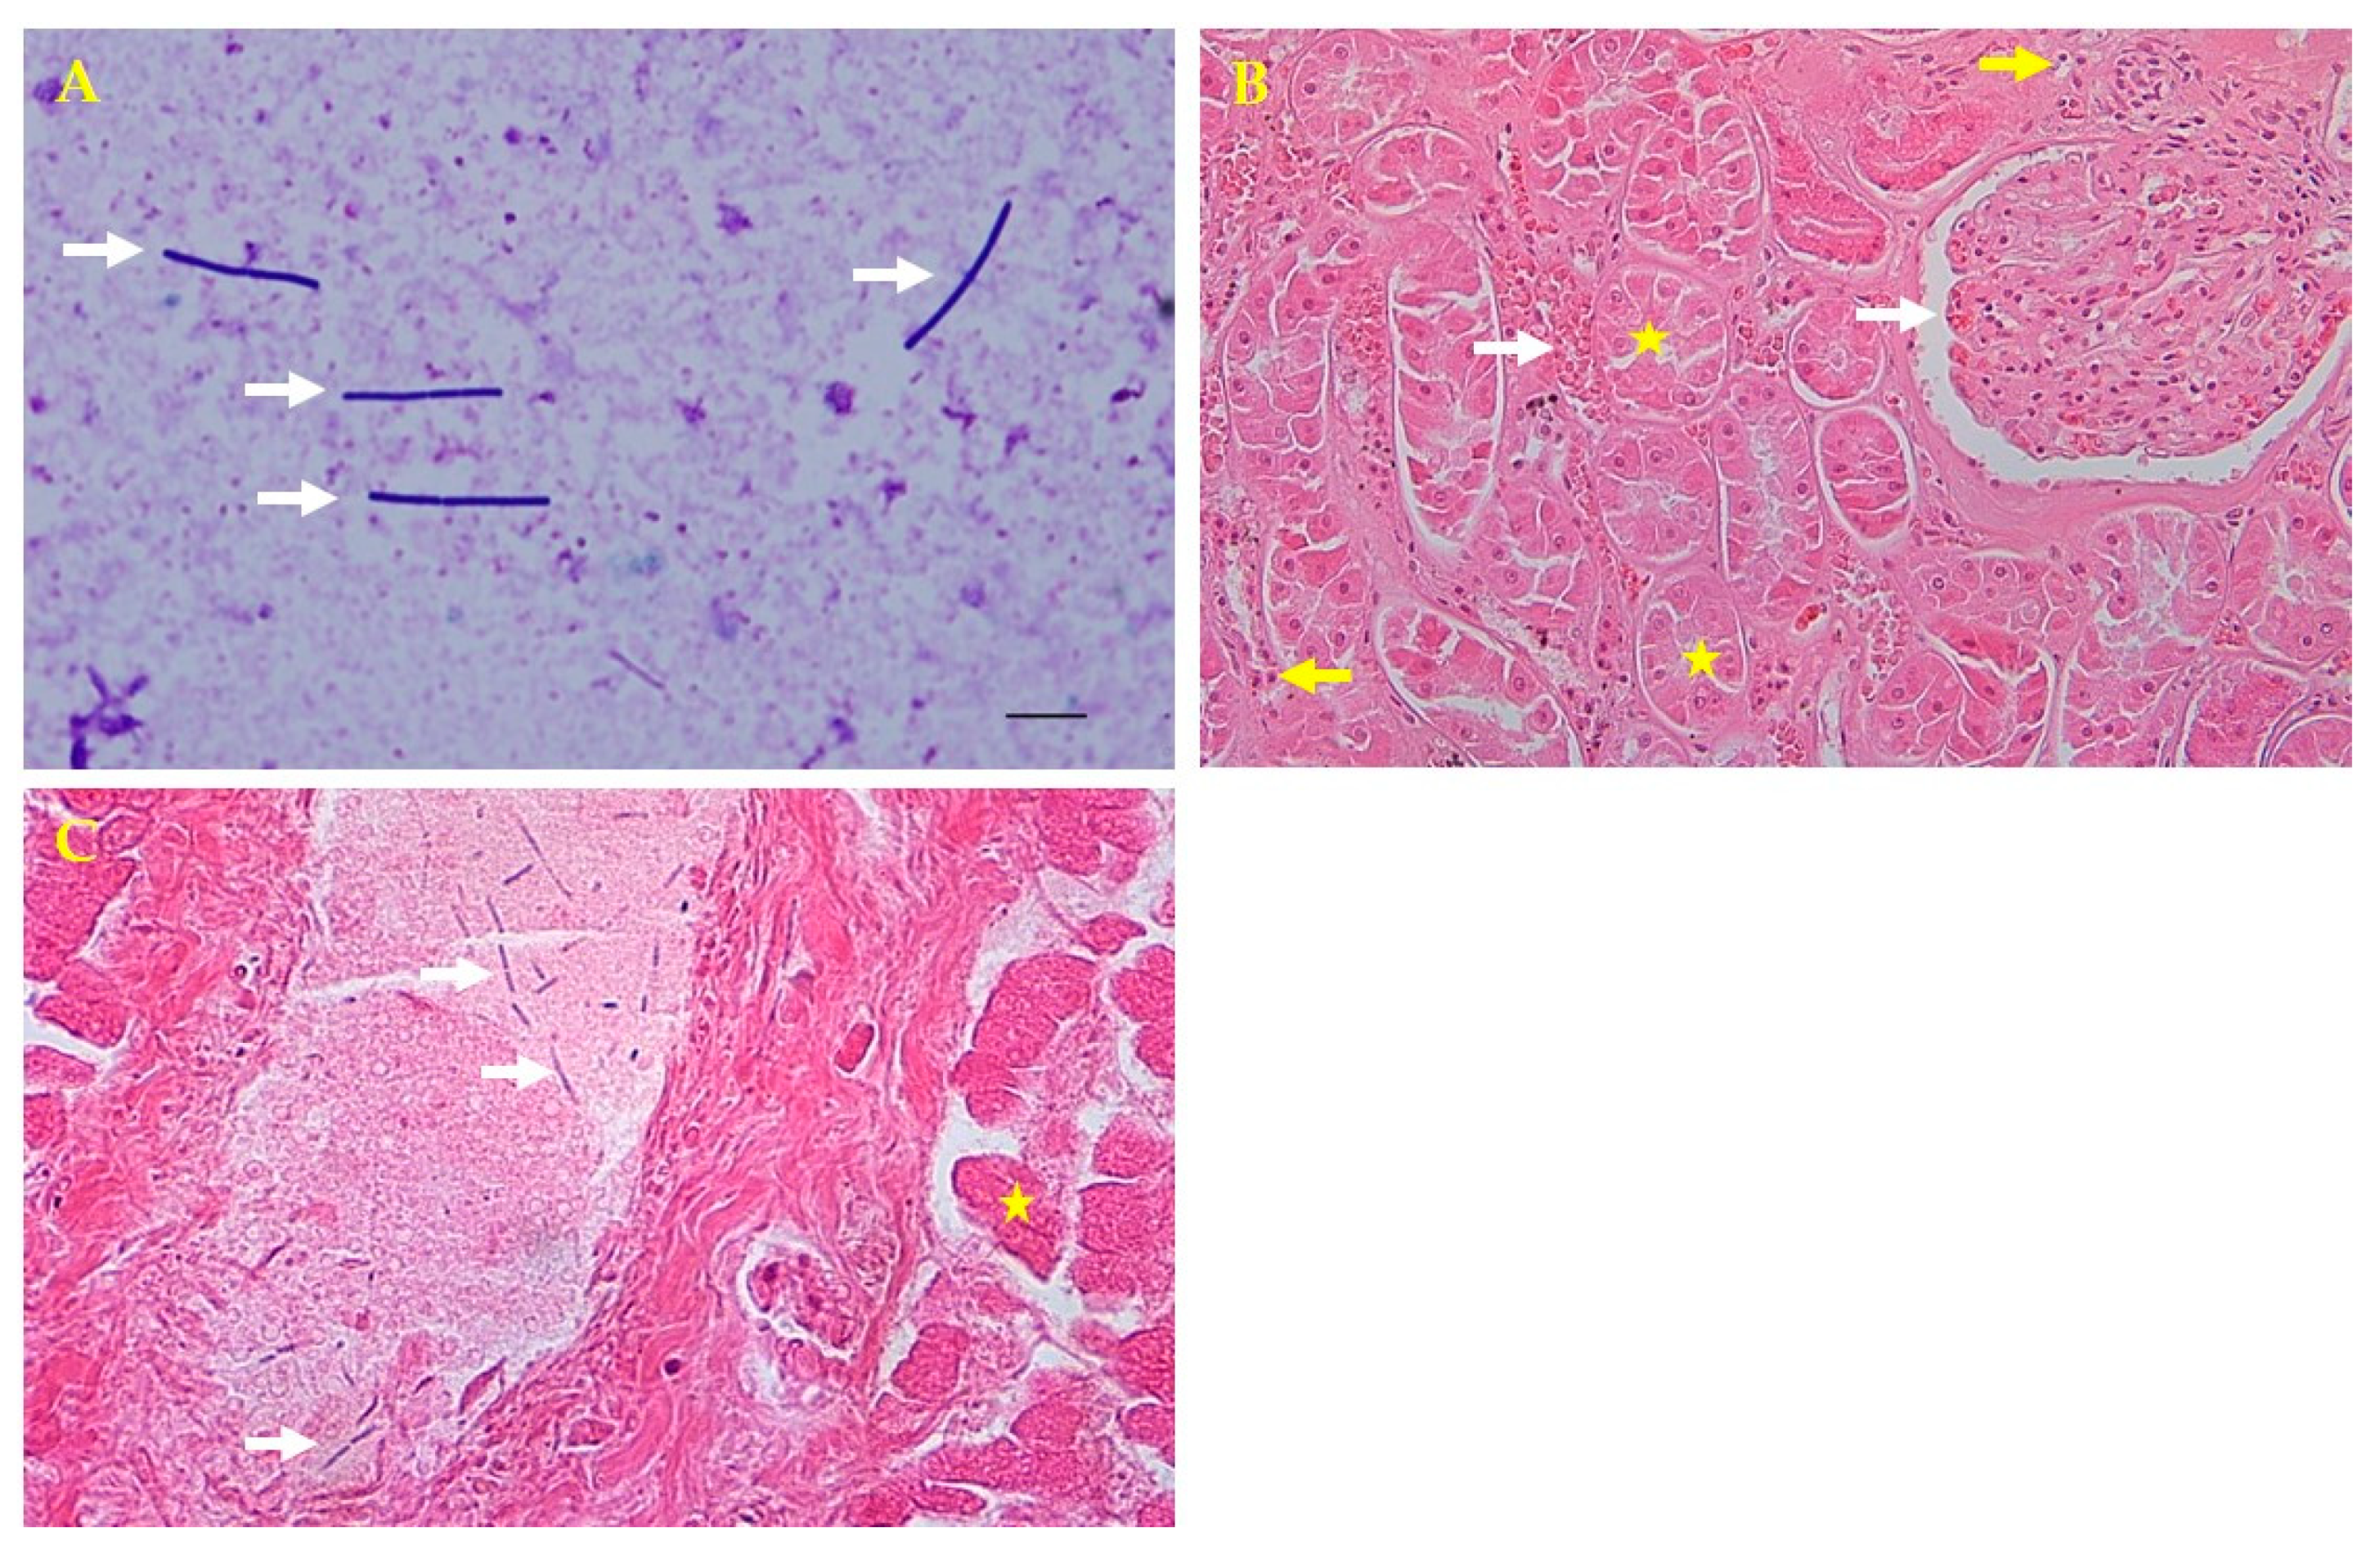

Figure 2.

Microscopic and histopathologic findings. (A) Direct smear from the liver parenchyma showing rod-shaped bacteria colonies by Giemsa staining (white arrows; 1000×). (B) Kidney tubular necrosis (yellow stars) and glomerular and intertubular congestion (white arrows) with inflammatory cells (yellow arrows) by hematoxylin and eosin (H&E) staining (200×). (C) Thread-like bacteria (white arrows) in the portal vein and hepatocellular necrosis in the liver (yellow star) by H&E staining (400×).

For the histopathologic analysis, tissue samples (liver, kidneys, spleen, and heart) were collected and fixed in 10% neutral buffered formalin for 2 weeks, embedded in paraffin, sectioned at 4 μm, and stained with hematoxylin and eosin for microscopic examination. Histopathologically, tubular necrosis, and glomerular congestion were observed in the kidneys. The interspaces between the renal tubules were found to be infiltrated with blood and inflammatory cells (Figure 2B). The liver portal vein had thread-like bacteria and hepatocellular necrosis (Figure 2C). Although autolysis is not entirely impossible, cells with normal nuclei were observed around some necrotic cells found in kidney tissues. Inflammatory cells were also observed around the tubules. In the presented photograph, congestion was observed around the glomerulus and tubules. Congestion and necrosis were observed in most of the kidneys, which are not presented.